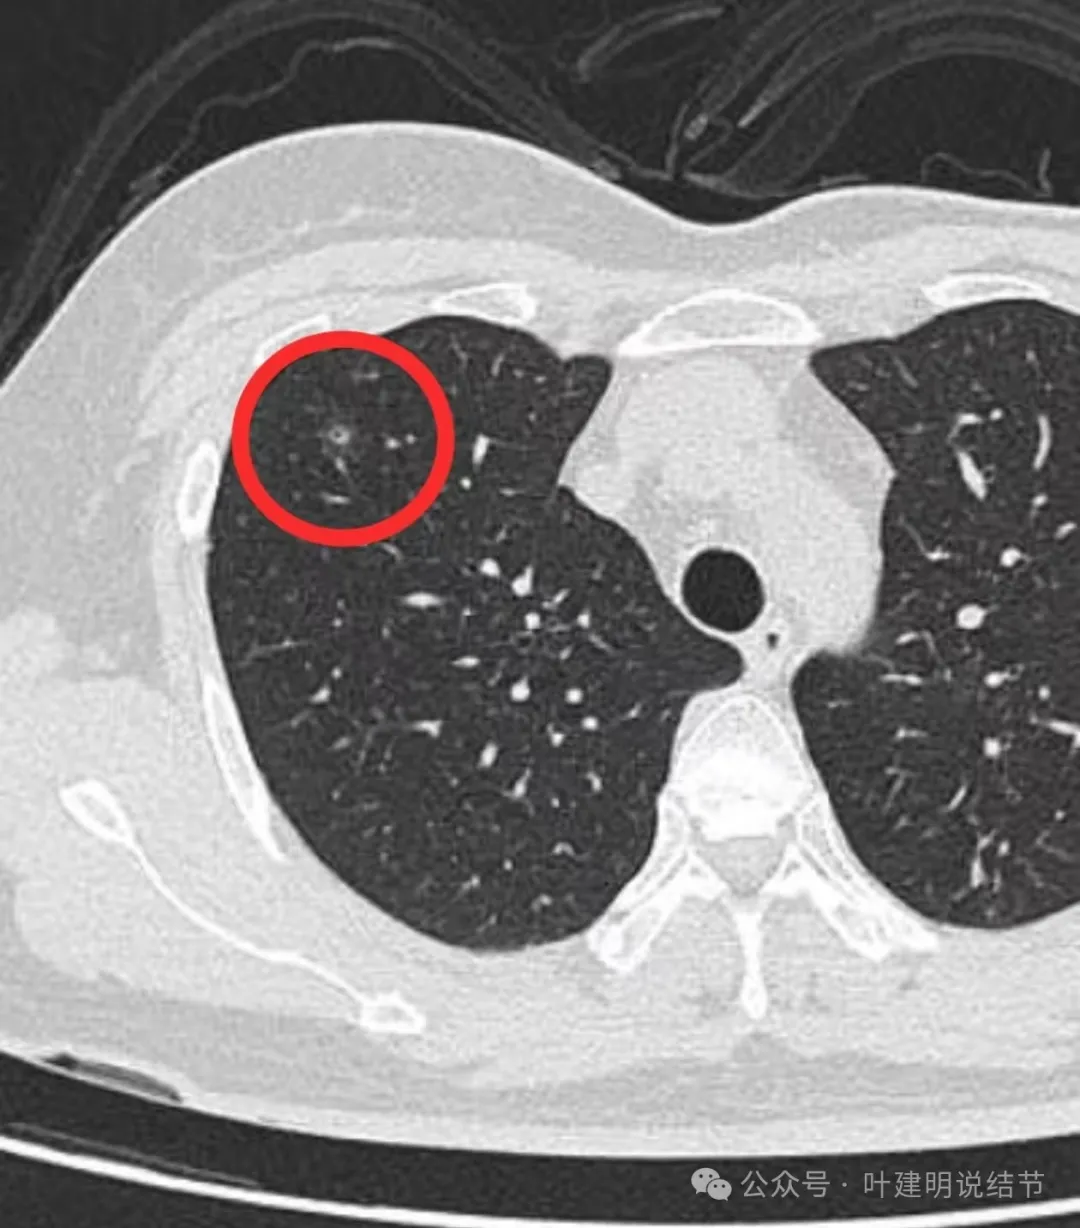

右上叶混合密度结节,此灶周围有晕(很淡而边界欠清的磨玻璃),中间有小空泡征,空泡的壁又是实性密度的,空泡内壁圆而较光滑,邻近有小血管走过。

病灶出现,轮廓不清,边缘显糊。

有细支气管通气征,沿扩张的细支气管两侧有密度较高的阴影,再外围有淡的边界不清的磨玻璃成分。

有血管经过病灶处,但距离这么近,血管却没有被影响或形成血管弯。绿色箭头处距病灶有一定距离,但也有淡而模糊的磨玻璃影。

病灶附近多发微小空泡样结构(砖色箭头),病灶边缘轮廓不清(如天蓝色箭头所示),病灶内部有实性密度伴空泡征的结节。

绿色箭头所示的磨玻璃影与主病灶并不相连的;主病灶轮廓不清;附近许多小空泡样结构;血管没有异常增粗或进入病灶内。

2023年8月时主病灶的样子,与2024年的几乎没有变化。